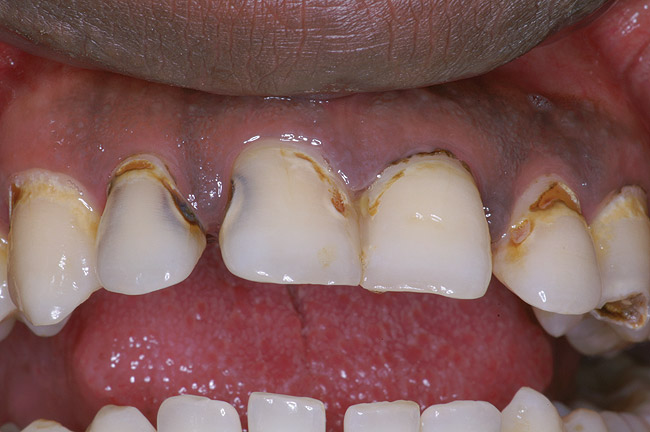

Fig. 1 Initial caries. Class V carious lesions.

Figure 1  Initial caries. Class V carious lesions.

Figure 1

Replacement of existing restorations is responsible for 75% of all operative dentistry.15,19 The reasons for placement and replacement of restorations of direct restorative materials include: primary caries (Figure 1 and Figure 2); recurrent caries (Figure 3); poor margins (Figure 4 and Figure 5); restoration fracture (Figure 6 and Figure 7); tooth fracture (Figure 8); esthetics (Figure 9); non-carious tooth structure lost (attrition, abrasion, abfraction, erosion) (Figure 10); and pain/sensitivity.